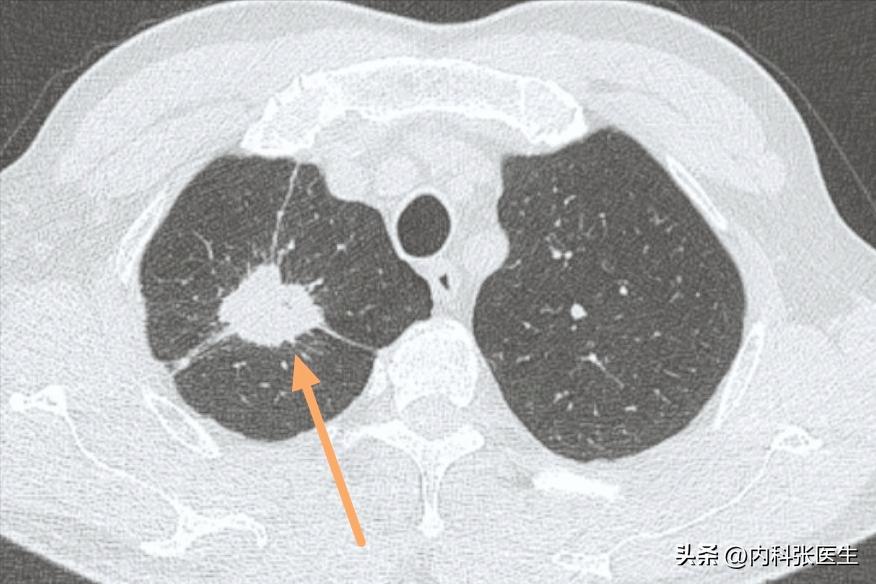

肺癌CT

咱们先说说什么是肺结节。其实,随着现在体检越来越普及,很多人都查出来肺里长了个小结节。有的结节是良性的,没啥大事;但有一类叫“恶性孤立性肺结节”(专业点叫“早期非小细胞肺癌”),这个可得千万当回事。

根据北京大学第一医院的一项权威研究(见文末参考文献),对172例恶性孤立性肺结节(也就是早期非小细胞肺癌)患者进行了长期随访,最长随访时间达10年。结果发现:

早期肺癌患者5年生存率高达89.9%,比晚期要高太多了!不同人群,癌症发展的速度差异很大。比如,年龄超过65岁的人、男性、体内肿瘤细胞增殖速度快(Ki-67增殖指数高)的人,癌症进展和恶化的可能性明显更大。那具体要多少年?其实,癌细胞从刚出现、长成能被影像学发现的结节,通常要数年时间。发展成直径2厘米左右的早期肺癌,可能又需要几年。而一旦进入晚期,进展就像“下坡路”一样加快。所以说,肺癌从早期到晚期,快的两三年,慢的五六年、甚至更久都有可能,这和每个人的体质、肿瘤的类型、生活习惯都有关系。